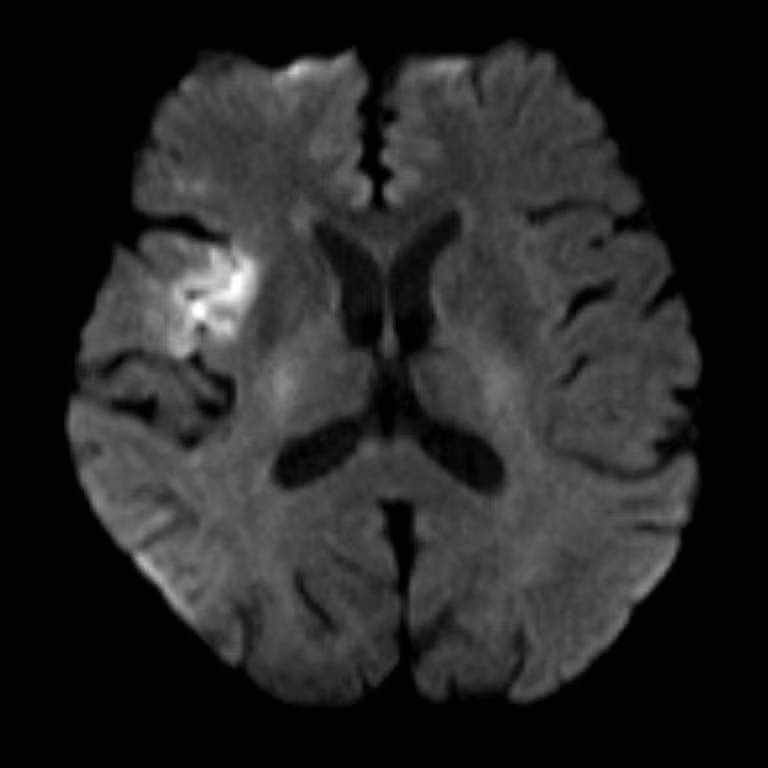

Hình MRI bệnh nhân T.L bị đột quỵ - Ảnh BVCC

Tại đây, ngay khi xác định được dấu hiệu đột quỵ, quy trình “báo động đỏ” lập tức được kích hoạt, quy tụ đội ngũ bác sĩ các chuyên khoa Cấp cứu, Nội thần kinh, Chẩn đoán hình ảnh. Trước đây, bệnh nhân có tiền sử tăng huyết áp và bệnh phổi tắc nghẽn mãn tính (COPD) nhưng không điều trị. Kết quả trên phim MRI cho thấy bệnh nhân bị đột quỵ nhồi máu não.